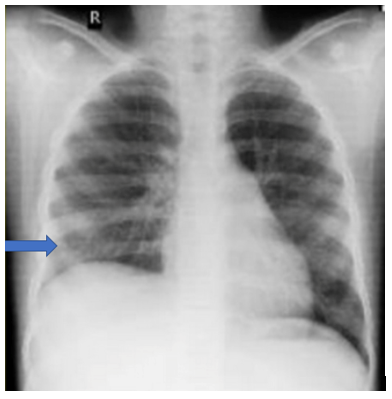

Therapeutic Intervention: As per the International Society of Pediatric Oncology (SIOP), her management plan included preoperative chemotherapy followed by radical nephrectomy and post-operative chemotherapy. She received 6 cycles of chemotherapy prior to surgery comprising of vincristine (1.5mg/m2), actinomycin D (45mcg/Kg) and adriamycin (50mg/m2). Her pleural effusion completely resolved after 4 weeks of chemotherapy without need of further thoracocentesis (Fig 3). She then underwent right radical nephrectomy. However, during surgery the mass was found to be densely adherent to the inferior venacava (IVC) throughout its length as well as to posterior aspect of liver and diaphragm. Some residual mass adherent to IVC was left behind. Histopathological examination of the specimen was suggestive of Wilms tumor (SIOP stage III) with no lymph nodal metastasis. In view of the residual disease, she received post-op radiotherapy with a total dose of 10.8 grays to the abdomen.

Figure 3: Chest x-ray showing complete resolution of pleural effusion after 4 weeks.